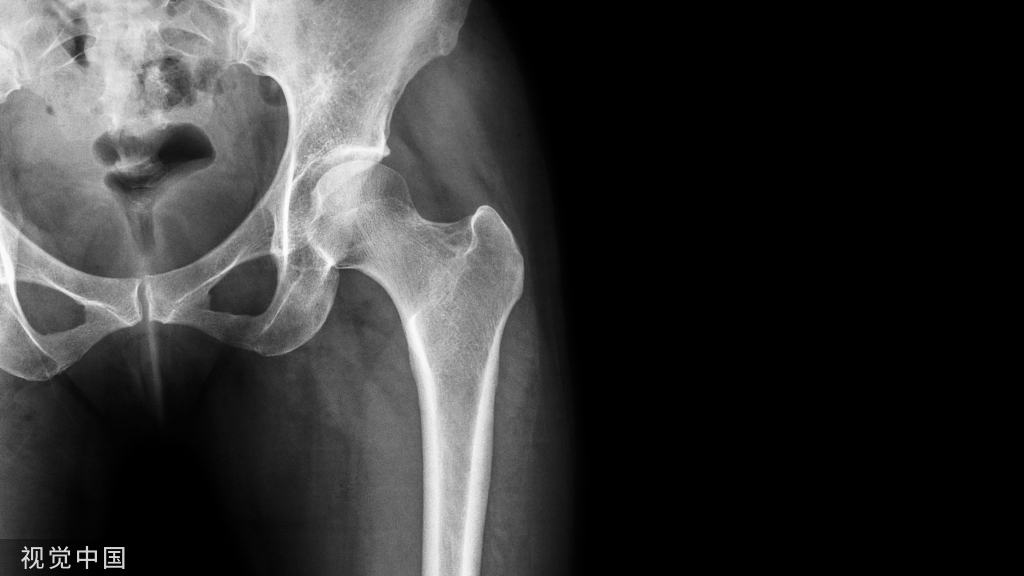

髋关节

左侧股骨大粗隆处见不规则透亮线影,骨折处无明显分离、移位。左侧股骨大粗隆骨折。踝关节